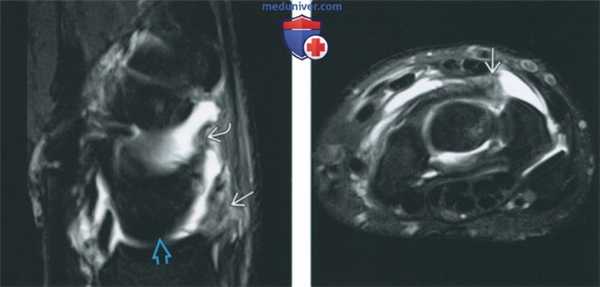

(Слева) МР-артрография в режиме PD FS, сагиттальный срез на уровне полулунной кости: определяются утолщенные луче-трехгранная и тыльная межзапястная в связки, которые имеют аморфную структуру с наличием прослоек жидкости между волокнами. Такая картина характерна для растяжения связок тыла запястья.

(Справа) МР-артрография в режиме PD FS, аксиальный срез через середину запястья, этот же пациент: визуализируются утолщенные связки, которые характеризуются гетерогенной структурой.

• Растяжение тыльных связок запястья:

о Нарушение целостности волокон связки, прослойки жидкости между волокнами

о Как правило, отмечается усиление интенсивности сигнала на Т2 ВИ вследствие отека, воспалительных изменений и кровоизлияний